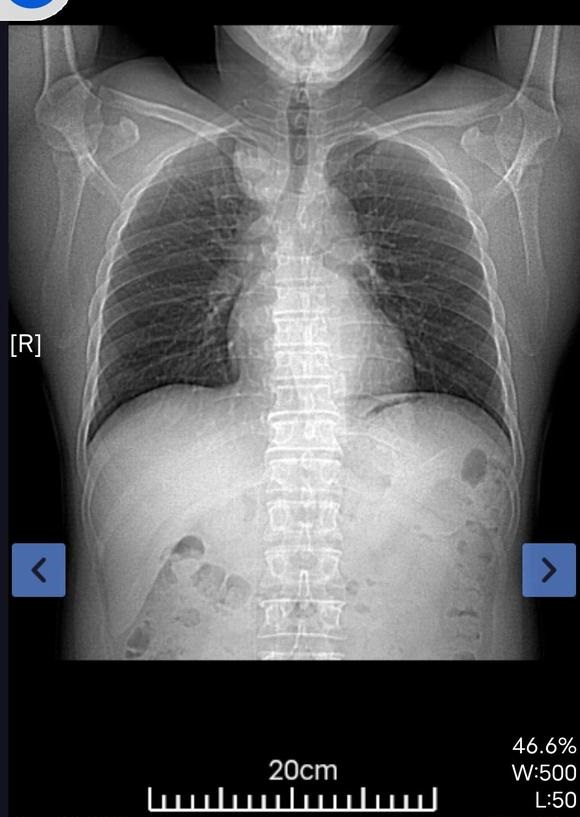

镜 02021-12-22 患者父亲10月底确诊肺癌中晚期,采用免疫疗法治疗。确诊的过程基本与我卖房换房的过程重叠,我大龄单身目前没有工作,父母的意思是...

北港永下 02021-12-21 患者家属我父亲体检时发现有肿块。到人民医院检查结果显示食管囊肿或支气管囊肿本来医生说不是很大的手术。几天前做了增强ct。又说有可...